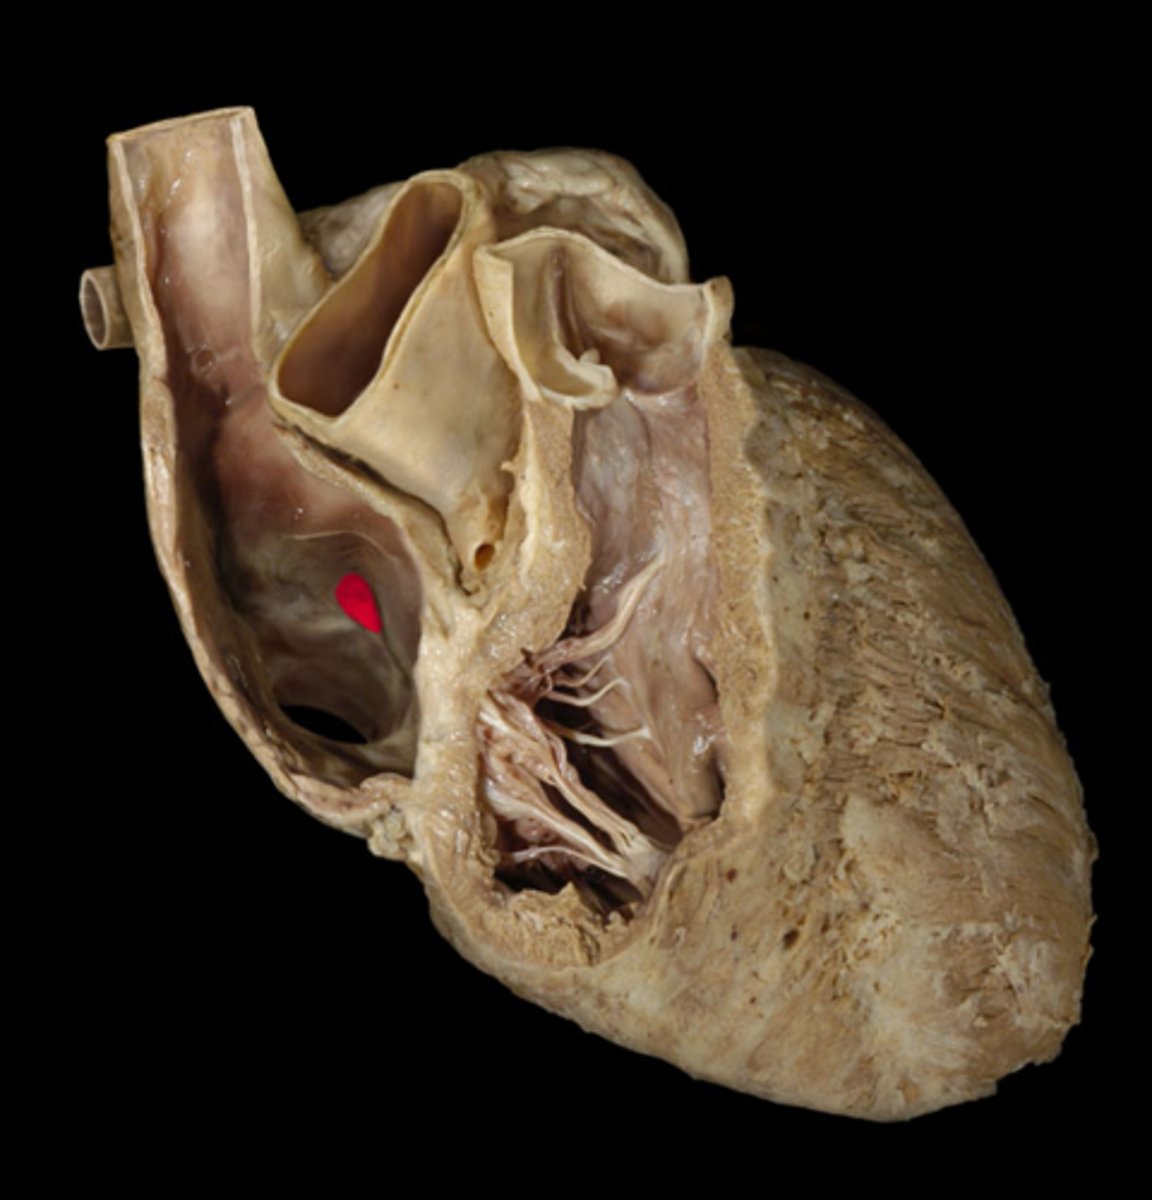

Fossa ovalis

depression

in R atrium, pinto bean buried in R atrium

H5

24

Pectinate muscle

st

stretch jeans on inside of right atrium

webbing on wall of R atrium

Sinus venarum

surface; on inside of right atrium, smooth part, by fossa ovalis

opening of the superior vena cava

opening; tip of probe, posterior side, smaller opening at top

H6

opening of the inferior vena cava

opening; posterior side, end of probe, bottom of shoe, smaller opening at back

Opening of the coronary sinus

opening: Hole below fossa ovalis, just stick tip of probe in